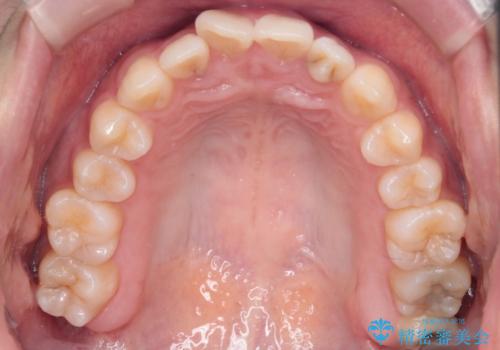

【インビザライン】前歯の凸凹を治したい

- 前歯の凸凹を主訴に来院されました。

インビザラインにて臼歯部の遠心移動を行いながら、できるだけ前歯が出ないように気を付けて治療を行っています。